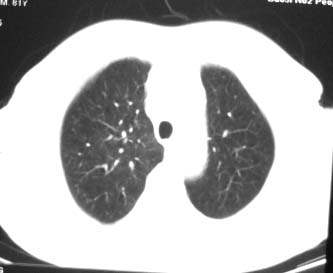

81 男 以头昏入院

两肺多发异常密度,其中双上肺病变主要为纤维增殖性改变;右中肺内侧段病变密度相对均匀,无恶性特征,周围可见卫星灶和浸润表现,邻近胸膜稍增厚,所见纵隔层面无肿大淋巴结和胸腔积液。提示结核性改变。如果可能建议强化。

右肺中叶团片影,似多病灶融合而成,密度不均匀,边界清楚,周围见明显的索条及小结节,左肺亦见斑片影,纵隔窗未见肿大淋巴结.多考虑:肺内慢性炎性病变伴纤维化.

两肺多发异常密度,其中双上肺病变主要为纤维增殖性改变;右中肺内侧段病变密度相对均匀,无恶性特征,周围可见卫星灶和浸润表现,邻近胸膜稍增厚,所见纵隔层面无肿大淋巴结和胸腔积液。提示结核性改变.

符合多叶多段多形态的特点.